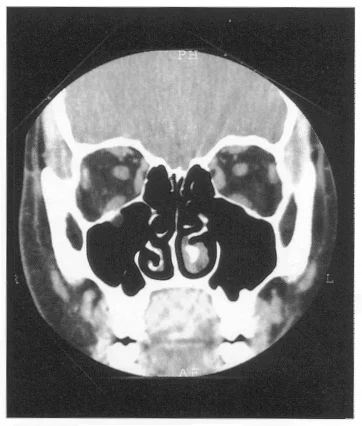

Floor Fractures

Orbital Fractures

Find the Fracture